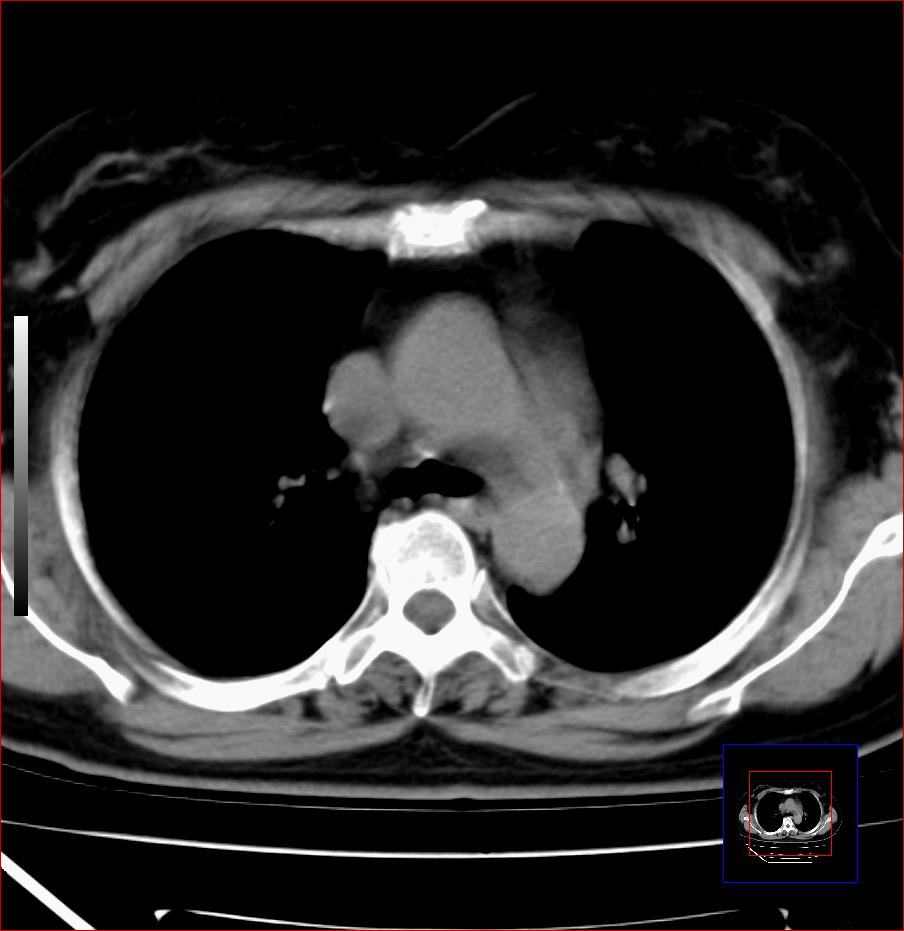

标题: CT25445:上段食管正常吗?

女,56岁,胸部体检,无不适。感觉食管壁略厚,最后约6mm.谢谢大家讨论,主要是自己亲人,疑神疑鬼的。主动脉弓旁淋巴结还有点肿大。

食管上三分之一段为横纹肌含气少或无 管壁可以厚些